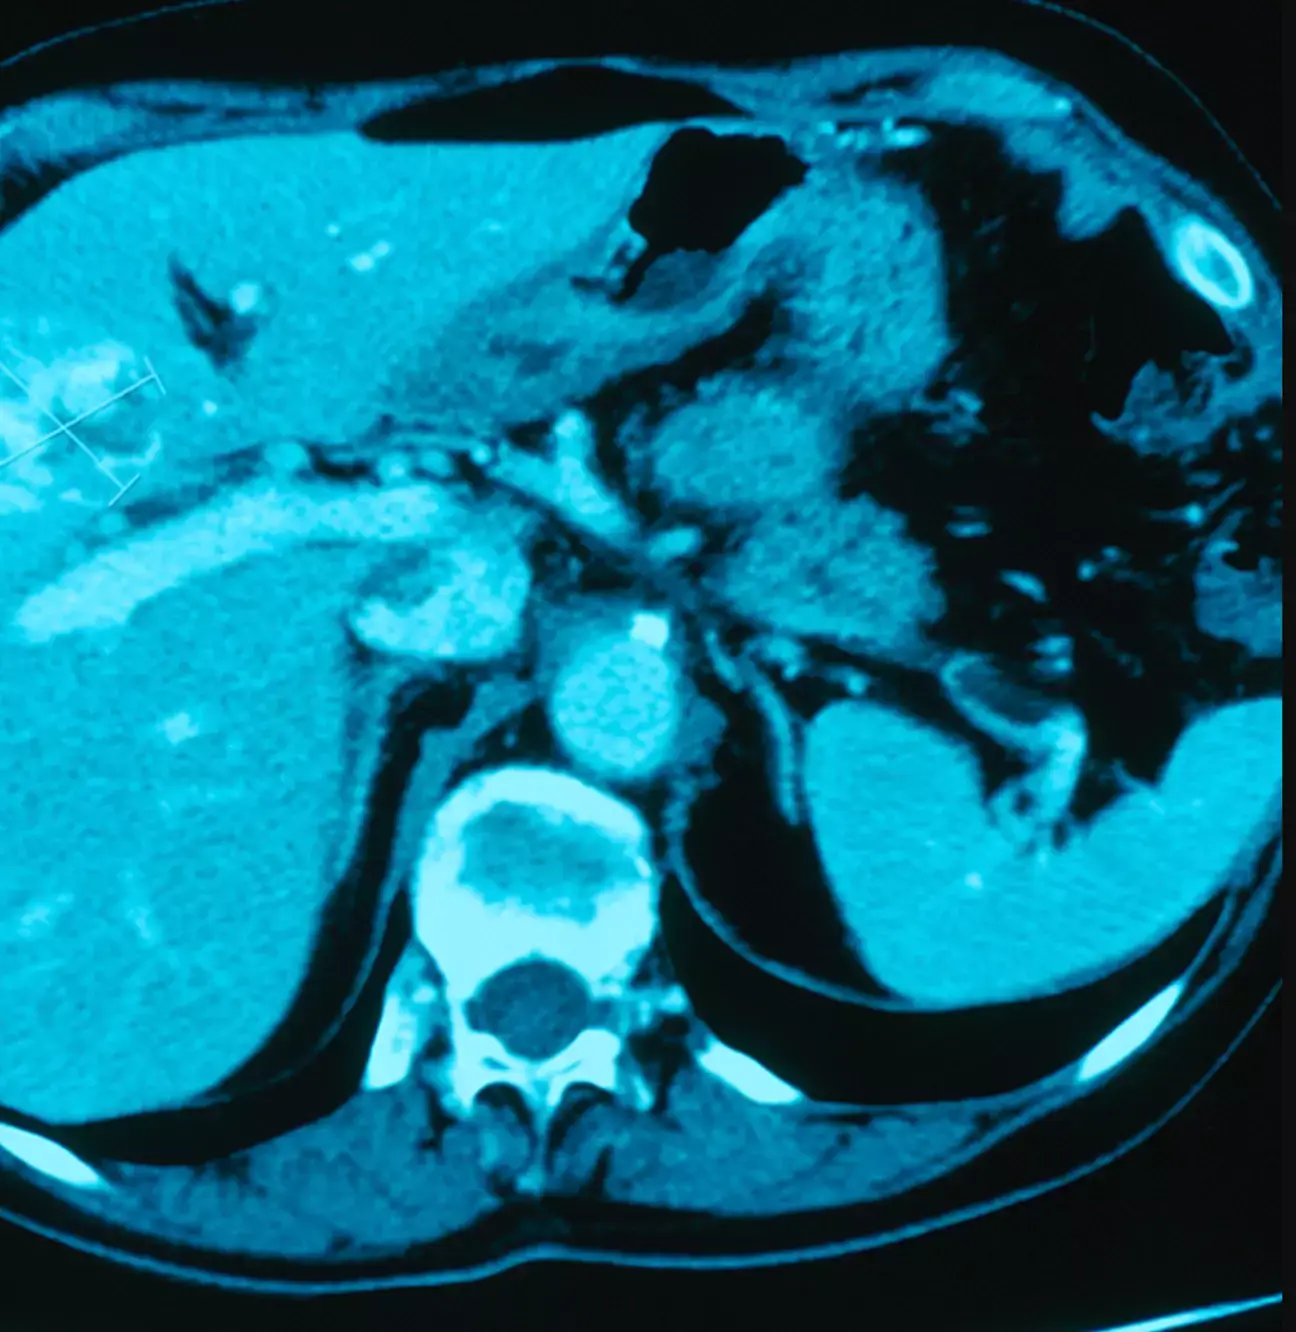

These parasites can cause cholangiocarcinoma, or bile duct cancer, which can obviously make you gravely ill.

Isaan has the highest reported rates of this disease in the world due to the heavy consumption of the raw fish meal.